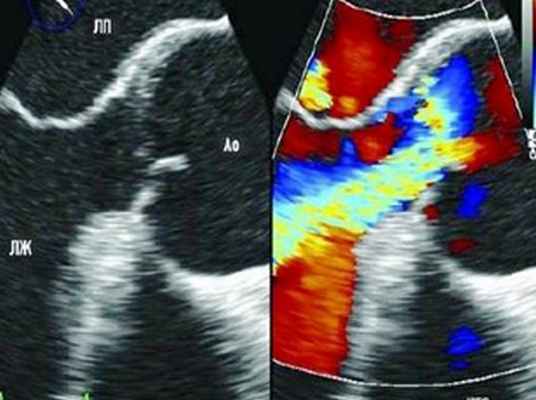

6. Как подтвердить диагноз? Какова роль чреспищеводной эхокардиографии?

Данные литературы свидетельствуют о высокой точности диагностики чреспищеводной эхокардиографией расслоений аорты. В некоторых центрах решение о необходимости операции принимается на основании данных только одного этого диагностического метода. Тем не менее аортография по-прежнему остается золотым стандартом.

Если позволяет время и больной стабилен, аортографию следует провести для подтверждения диагноза, верификации тина расслоения (восходящий или нисходящий), состояния клапана аорты и коронарных артерий. Фактически оба диагностических исследования могут взаимно дополнять друг друга: чреспищеводная эхокардиография подтверждает диагноз, а при помощи аортографии уточняется расположение дефекта, состояние аортального клапана и коронарных артерий.

- Ультразвуковые методы исследования – при наличии аневризмы восходящего отдела аорты (I и II тип расслоения) или наличия пороков аортального клапана достаточно информативным методом диагностики является ЭХО-кардиография (УЗИ-сердца).